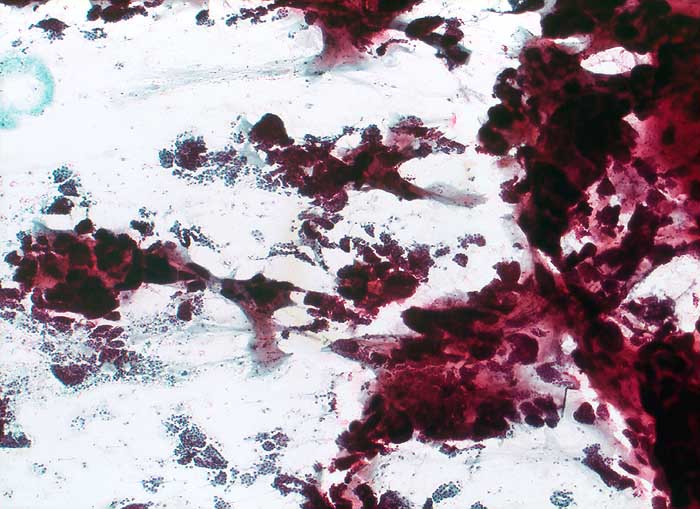

Einleitung

Homogene oder schlierenförmige extrazelluläre Schleimmassen mit Inseln von Tumorzellen mit geringen Kernatypien sind pathognomonisch für das muzinöse Mammakarzinom. Die Zellzahl ist meist nicht sehr hoch. Die Zellen liegen einzeln oder in kleinen kugeligen oder pseudopapillären Verbänden. Der Schleim erscheint in der Pap Färbung blau-grau bis rötlich. Siegelringkarzinome zeigen grössere intrazytoplasmatische Schleimvakuolen.

Unten werden zwei Beispiele von typischen muzinösen Karzinomen gezeigt.